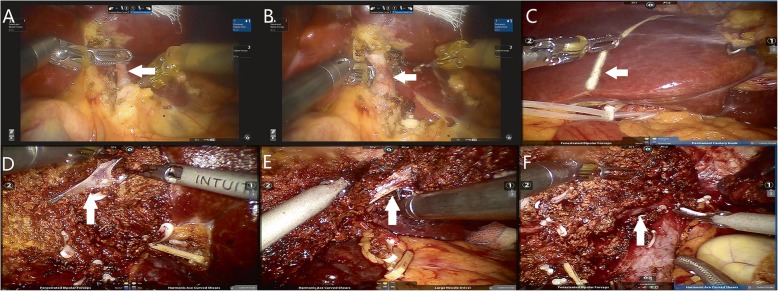

Fig. 5.

The main procedures of robotic left hemihepatectomy. a The left hepatic artery (A, arrow) was dissected and sectioned with clips and an ultrasound scalpel. b The left branch of the portal vein (B, arrow) was dissected and sectioned with clips and an ultrasound scalpel. c The ischaemic demarcation line (C, arrow) was incised by using a monopolar hook. d The branches of the middle hepatic vein (D, arrow) were dissected and sectioned with clips and an ultrasound scalpel. e The left hepatic vein was dissected and sectioned by using a linear vascular endo-stapler (E, arrow). f Hepatic cross section after hemihepatectomy and the middle hepatic vein (F, arrow)

Fig. 6.

The main procedures of robotic right hemihepatectomy. a The right hepatic artery (A, arrow) was dissected and sectioned with clips and an ultrasound scalpel. b The right branch of the portal vein (B, arrow) was dissected and sectioned with clips and an ultrasound scalpel. c The ischaemic demarcation line (C, arrow) was incised by using a monopolar hook with the application of indocyanine green (ICG) fluorescence imaging. d The branches of the middle hepatic vein (D, arrow) were dissected and sectioned with clips and an ultrasound scalpel. e The right hepatic vein was dissected and sectioned by using a linear vascular endo-stapler (E, arrow). f Hepatic cross section after hemihepatectomy and branches of the middle hepatic vein (F, arrow)